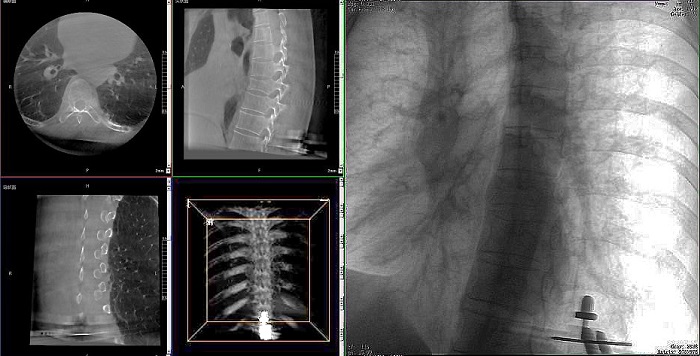

①機(jī)器人輔助胸椎手術(shù)操作難點(diǎn)之圖像采集

胸椎緊鄰肺部,患者的呼吸運(yùn)動(dòng)會(huì)造成椎節(jié)的相對(duì)移動(dòng),獲取清晰、穩(wěn)定的影像較為困難。高質(zhì)量的影像是精準(zhǔn)導(dǎo)航的重要前提,胸椎手術(shù)中,如果呼吸造成的移動(dòng)無法得到有效控制,則會(huì)降低導(dǎo)航的精度,增加手術(shù)風(fēng)險(xiǎn)。人體深吸氣胸圍與深呼氣胸圍的差值約為6~8厘米。

普愛醫(yī)療手術(shù)導(dǎo)航定位系統(tǒng)解決方案

高清三維成像:普愛醫(yī)療精研三維成像技術(shù)13年,自研的三維C形臂可為手術(shù)提供清晰、穩(wěn)定的三維圖像,為醫(yī)生精準(zhǔn)開展胸椎手術(shù)提供影像保障。

亞毫米級(jí)精度:普愛醫(yī)療三維C形臂+骨科手術(shù)機(jī)器人,基于同一技術(shù)平臺(tái)研發(fā),借助一體化自適應(yīng)配準(zhǔn)及無損圖像傳輸技術(shù),整體協(xié)同性更高,精度可達(dá)亞毫米級(jí)。

快速掃描:麻醉師通過適當(dāng)?shù)暮粑刂?,配合三維C形臂的快速掃描模式,可以在短時(shí)間內(nèi)完成圖像采集,減少因呼吸運(yùn)動(dòng)造成的圖像干擾。